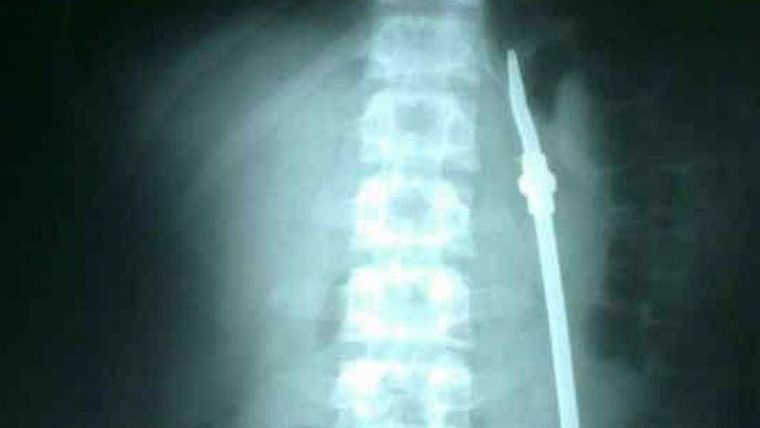

Luego de algunos estudios, los médicos detectaron que el joven efectivamente se había tragado una bombilla, pero fue intervenido quince días después. Cuando finalizó la operación, el detenido aprovechó un descuido de la custodia y se fugó.